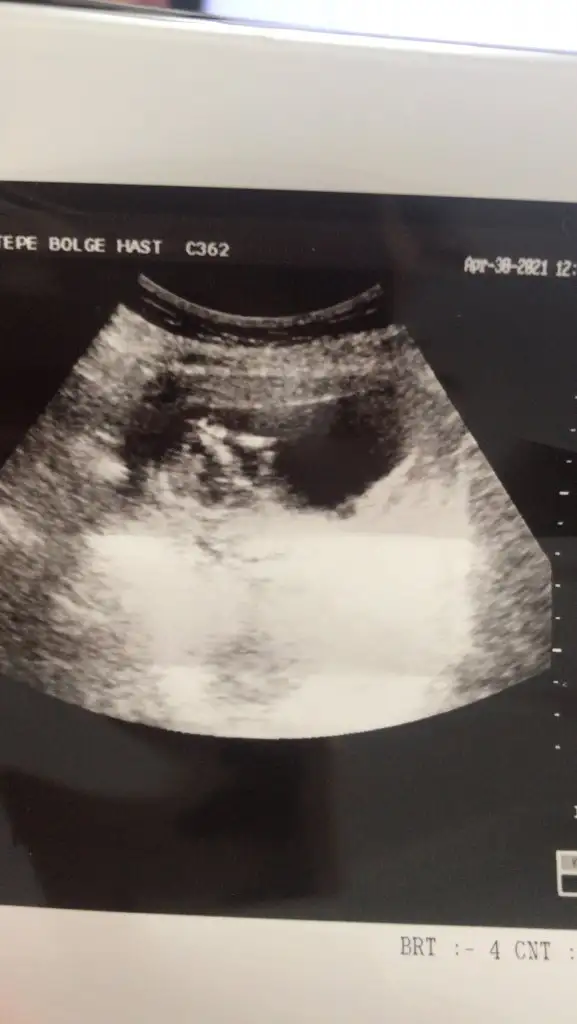

14+3 tahminde bulunurmusunuz🤦‍♂️

• USER_SCOPED_TEMP_DATA_MSGR_PHOTO_FOR_UPLOAD_1619699855146_6793513581238554568.webp

USER_SCOPED_TEMP_DATA_MSGR_PHOTO_FOR_UPLOAD_1619699855146_6793513581238554568.webp

16,7 KB · Görüntüleme: 69

• USER_SCOPED_TEMP_DATA_MSGR_PHOTO_FOR_UPLOAD_1619699207153_6793510863365994738.webp

USER_SCOPED_TEMP_DATA_MSGR_PHOTO_FOR_UPLOAD_1619699207153_6793510863365994738.webp

24,1 KB · Görüntüleme: 67